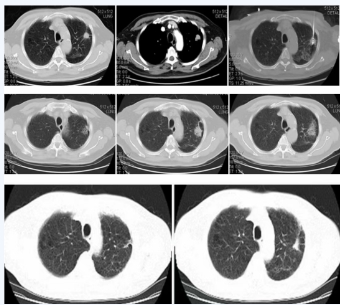

影像资料

左肺上叶病灶消融术后

36个月复查病灶缩小呈瘢痕改变